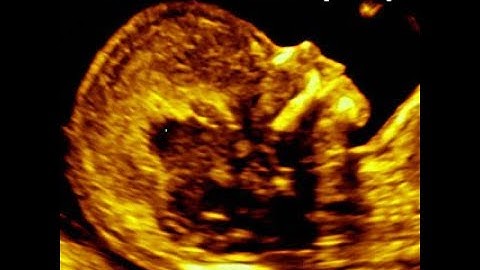

How to Measure Nuchal Translucency (NT) On Ultrasound | First Trimester NT Screening | Fetal USG